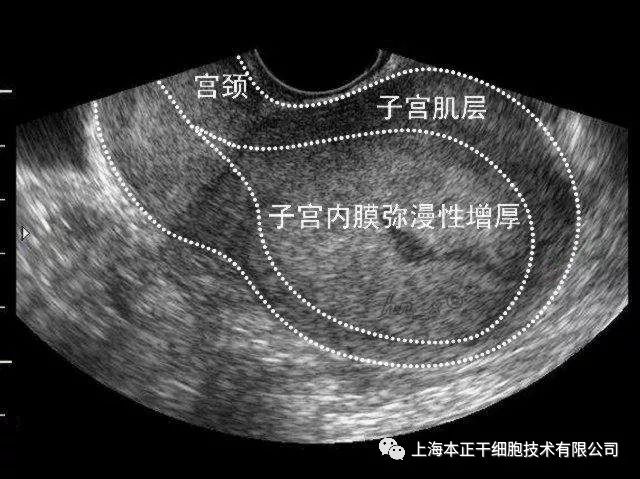

频繁的宫腔操作、感染及部分药物的使用一旦损伤子宫内膜基底层,会使子宫内膜细胞和腺体再生障碍,新生血管形成受损,子宫内膜难以实现自我修复。临床上常见的薄型子宫内膜和宫腔粘连(IUA)即是子宫内膜损伤后修复障碍的结果。虽然目前对于薄型子宫内膜的评价尚无统一标准,但多数学者认为,薄型子宫内膜是指子宫内膜厚度低于胚胎着床所需的阈厚度,通常子宫内膜厚度>7mm是保证胚胎着床的前提。有研究表明,妊娠率与病人的年龄和胚胎质量关系不大,但却随着子宫内膜厚度的增加而增加。薄型子宫内膜病人通常对药物呈低反应或无反应状态,且导致子宫内膜容受性降低'影响胚胎种植,增加流产的风险,是导致不孕的重要原因之一。

子宫内膜基底层严重受损是导致(IUA)形成的主要原因,据报道超过90%的IUA是由于子宫内膜损伤后病理性修复所致。近年来,很多学者提出子宫内膜损伤后再生修复困难,可能与子宫内膜基底层的干细胞数量减少或缺失,亦或是功能受损有关。而外源性的补充干细胞或许成为子宫内膜损伤后修复的新的治疗方法。

图1:患者移植前子宫内膜厚度

图2:同一患者移植后子宫内膜厚度